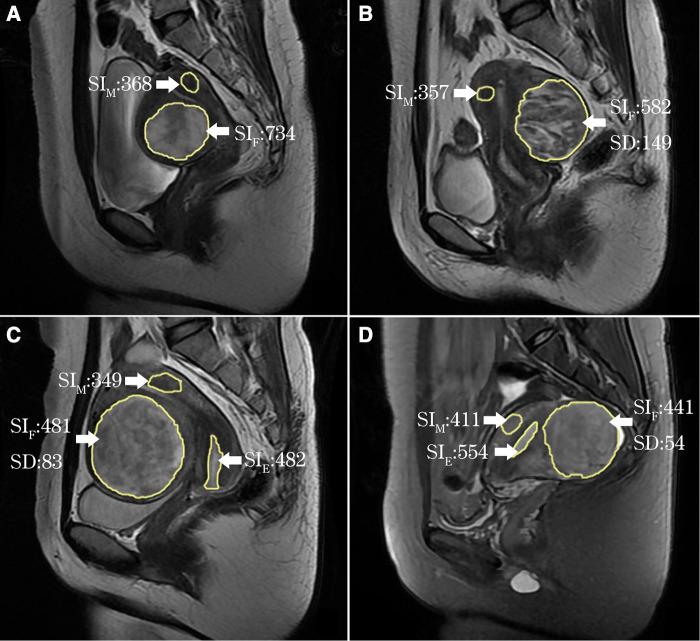

339 women with 368 hyperintense uterine fibroids on T2WI who underwent single-session HIFU ablation were enrolled, including 283 patients with 303 fibroids in the single-session HIFU (sHIFU) group and 56 patients with 65 fibroids in the HIFU pretreated with GnRH-a (Gn-HIFU) group. The signal intensity (SI) value and standard deviation (SD) value were measured based on T2WI, and the fibroids were further subdivided into heterogeneous hyperintense fibroids, slightly homogeneous hyperintense fibroids and markedly homogeneous hyperintense fibroids as 3 subgroups (HHF, sHHF and mHHF group respectively). Treatment time, sonication time, dose, non-perfused volume (NPV), NPV per sonication time, non-perfused volume ratio (NPVR), energy effect ratio (EEF) and adverse events were recorded.

纳入339例接受单次HIFU消融的T2WI上有368个高信号子宫肌瘤的女性,其中单次HIFU(sHIFU)组283例患者有303个肌瘤,GnRH-a预处理的HIFU(Gn-HIFU)组56例患者有65个肌瘤。基于T2WI测量信号强度(SI)值和标准差(SD)值,并将肌瘤进一步细分为异质性高信号肌瘤、轻度均匀性高信号肌瘤和显著均匀性高信号肌瘤作为3个亚组(分别为HHF、sHHF和mHHF组)。记录治疗时间、超声照射时间、剂量、无灌注体积(NPV)、每超声照射时间的NPV、无灌注体积比(NPVR)、能量效应比(EEF)和不良事件。